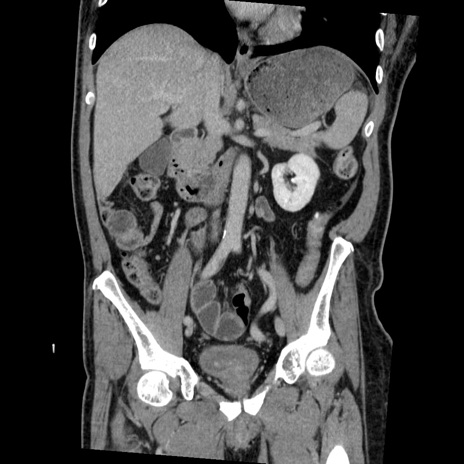

症例22(冠状断像)

【症例】50歳代男性

【主訴】腹痛

【現病歴】AVMからの被殻出血のため回復期リハ病棟入院中。 本日午後3時頃急に下腹部痛が出現した。

【既往歴】AVM、被殻出血、虫垂炎、高血圧

【身体所見】意識晴明、左半身不全麻痺、会話の理解は良好、36.5°C、腹部:膨隆、全体に板状硬、下腹部正中に圧痛点あり、反跳痛-、筋性防御不明、右下腹部にope scar

【データ】WBC 9400、CRP 0.06